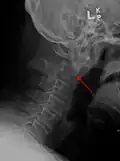

A fracture of both pedicles of the axis is termed a Hangman's fracture.

Fractures of the dens are classified into three categories according to the Anderson Alonso system:

- Type I fracture - Extends through the tip of the dens. This type is usually stable.

- Type II fracture - Extends through the base of the dens. It is the most commonly encountered fracture for this region of the axis. This type is unstable and has a high rate of non-union.

- Type III fracture - Extends through the vertebral body of the axis. This type can be stable or unstable and may require surgery.[1]

-

A fracture of the base of the dens as seen on plain X-ray -

A fracture of the base of the dens as seen on CT -

Type 3 odontoid fracture -

Type 2 dens fracture